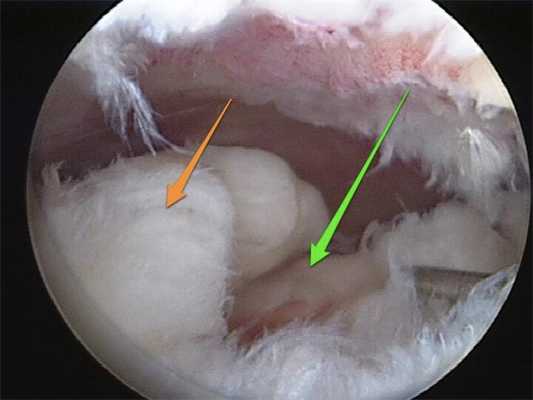

Артроскопия коленного сустава при повреждении менисков: описание методов и техник

При повреждениях менисков используют несколько видов артроскопических техник:

- накладывание шва;

- пластика мениска;

- частичная резекция нестабильных фрагментов мениска;

- тотальная менискэктомия (полное удаление).

Сегодня врачи отдают предпочтение артроскопическому восстановлению мениска, поскольку оно дает лучшие клинические и рентгенологические результаты, чем частичная и полная менискэктомия. Целостность мениска восстанавливают путем наложения шва или с помощью пластики. Такая операция позволяет стабилизировать движения в суставе и добиться равномерного распределения осевой нагрузки на суставные поверхности бедра и голени. А это, в свою очередь, снижает риск последующего развития остеоартроза.